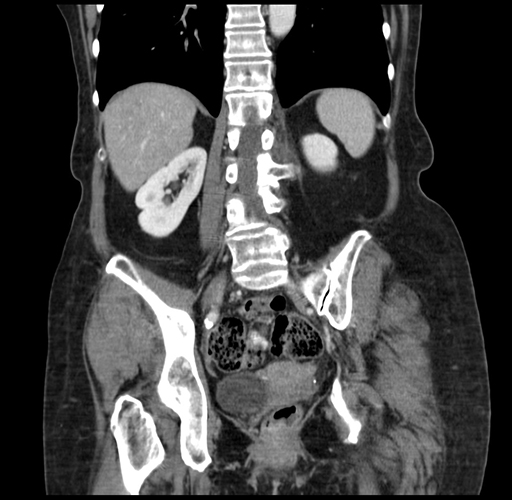

Coronal Venous